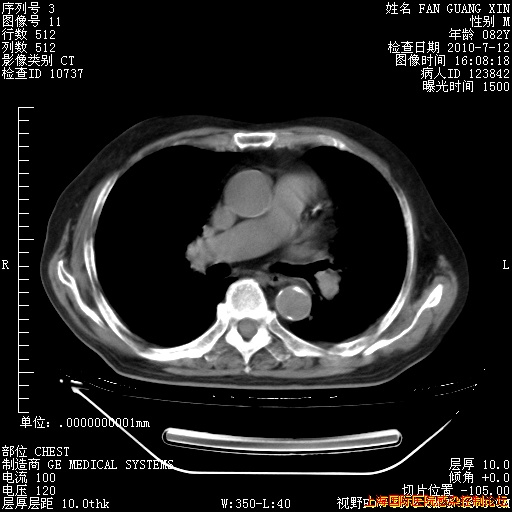

6月12日纵膈窗

今天复查CT

今天CT

整整相隔30天的肺部CT好像有所好转啊。甲强龙减量第3天,需要观察体温。